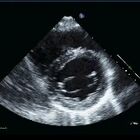

Welcome to ECHOpedia,

a free echocardiography textbook, designed for medical professionals

such as cardiologists and echocardiography technicians.

The ECHO Textbook

Browse the illustrated

ECHO Textbook